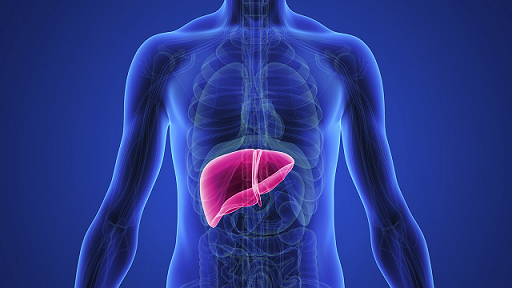

يذكر أن تليف الكبد مرض مزمن غير قابل للعلاج بصورة تامة يصاحبه استبدال نسيج الكبد المتني بنسيج ضام ليفي لا رجعة فيه. في حين يسبب التليف تضخم أو تقلص حجم الكبد ويصبح أعلى كثافة وسطحه خشنأ.